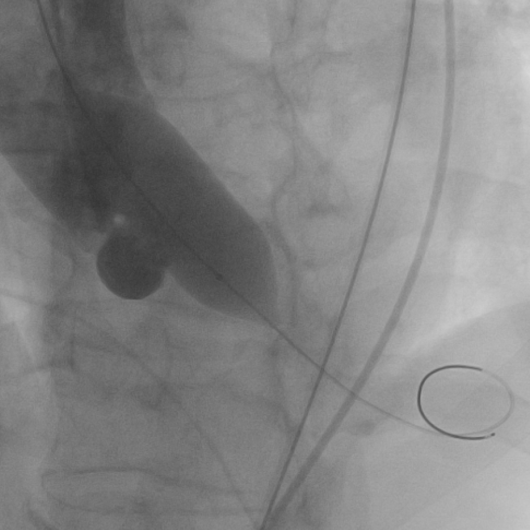

12月31日首都医科大学附属北京同仁医院心血管中心郭彩霞教授团队顺利完成首例TAVR手术。术中22mm球囊预扩冠脉不显影随即进行左冠冠脉烟囱支架保护,植入VenusA Plus可回收L26瓣膜,植入后位置良好,跨瓣压差近乎为零,整个手术一气呵成,手术取得圆满成功,手术后患者状态良好,成功救治82岁高龄患者。体现了心血管中心团队的综合救治能力,标志着在结构性心脏病的微创治疗方面达到国内先进水平。